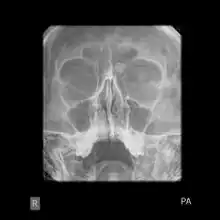

X-ray skull: Osteoma of the frontal sinus

Medical imaging such as X-ray, CT scan and MRI show dense, clearly defined, round white tumors attached to bone.[1] They may be diagnosed when having medical imaging for another reason.[3] Osteomas of the paranasal sinuses and skull base can be diagnosed using CT-scan without intravenous contrast, allowing its size and relation to nearby important structures to be assessed.[3] A biopsy is not usually required.[3]

Medical imaging such as X-ray, CT scan and MRI show dense, clearly defined, round white tumors attached to bone.[1] They can be left alone if not troubling, and surgically cut out if pressure symptoms.[1] The surgery may be possible through the nose, without making a large cut.[3]